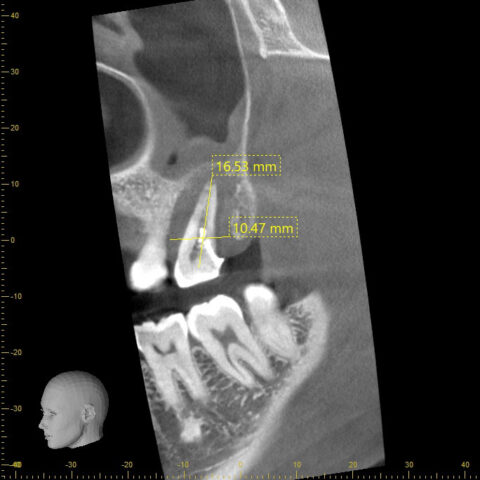

初診時CT

初診時の歯根周囲の骨の喪失状態をCTにて確認